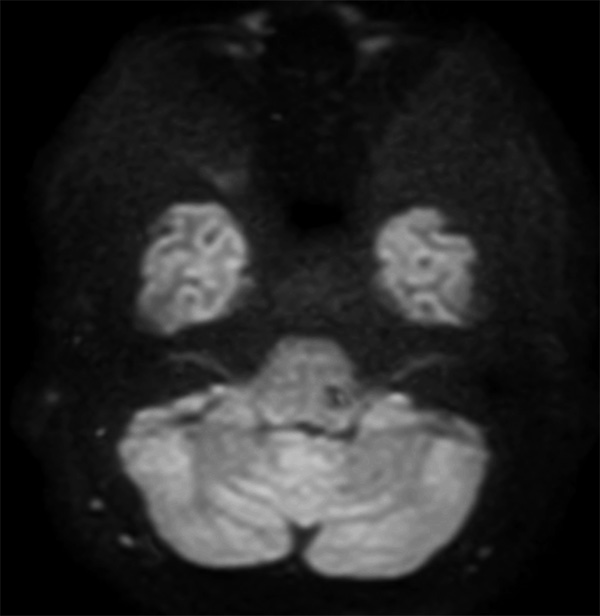

Comprehensive Brain imaging at 3.0T

• Clinical Application